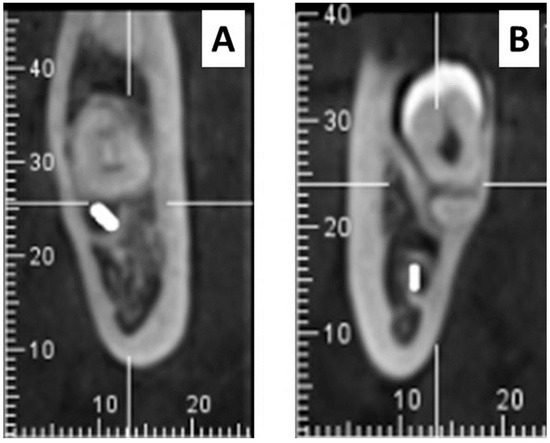

Attempting to Determine the Relationship of Mandibular Third Molars to the Mandibular Canal on Digital Panoramic Radiography; Using CBCT as Gold Standard

by Hilal Isra Erkan, Osman Yalcin, Umut Pamukcu and Kahraman Gungor

(1) Background: It is important to know, radiologically, the relationship of Mandibular third molars (M3) to the mandibular canal to minimize postoperative complications by causing damage to the inferior alveolar vessels and nerve during extraction. This study aimed to evaluate the usability of various image analyses or high-risk radiographic findings in determining the relationship of M3s to the mandibular canal on Digital Panoramic Radiography (DPR). (2) Methods: DPRs of 60 patients with bilateral mandibular M3s in the dental arch, determined one of them to be related to the mandibular canal unilaterally by Cone Beam Computed Tomography (CBCT), were included. The high-risk radiological signs of M3s and Fractal Analysis (FA) and Histogram Analysis (HA) measurements of the trabecular bone around the M3s’ roots were compared. The Independent t-test, Kolmogorov–Smirnov, Mann–Whitney U, and Chi-Square tests were used for statistical analyses. (3) Results: DPR signs, such as radiolucency and bifurcation at the root apex, discontinuity of the mandibular canal cortex, and superimposition of the tooth root and mandibular canal, were observed statistically significantly more frequently for mandibular canal-related M3s (p < 0.05). As an objective image analysis, Lacunarity showed a statistically significant difference between related and unrelated M3s for measurements made inside and outside the mandibular canal (p < 0.05). (4) Conclusions: This study demonstrated that the discontinuity of the mandibular canal cortex and Lacunarity measured on DPR could help determine the relationship of the mandibular M3s to the mandibular canal. Full article